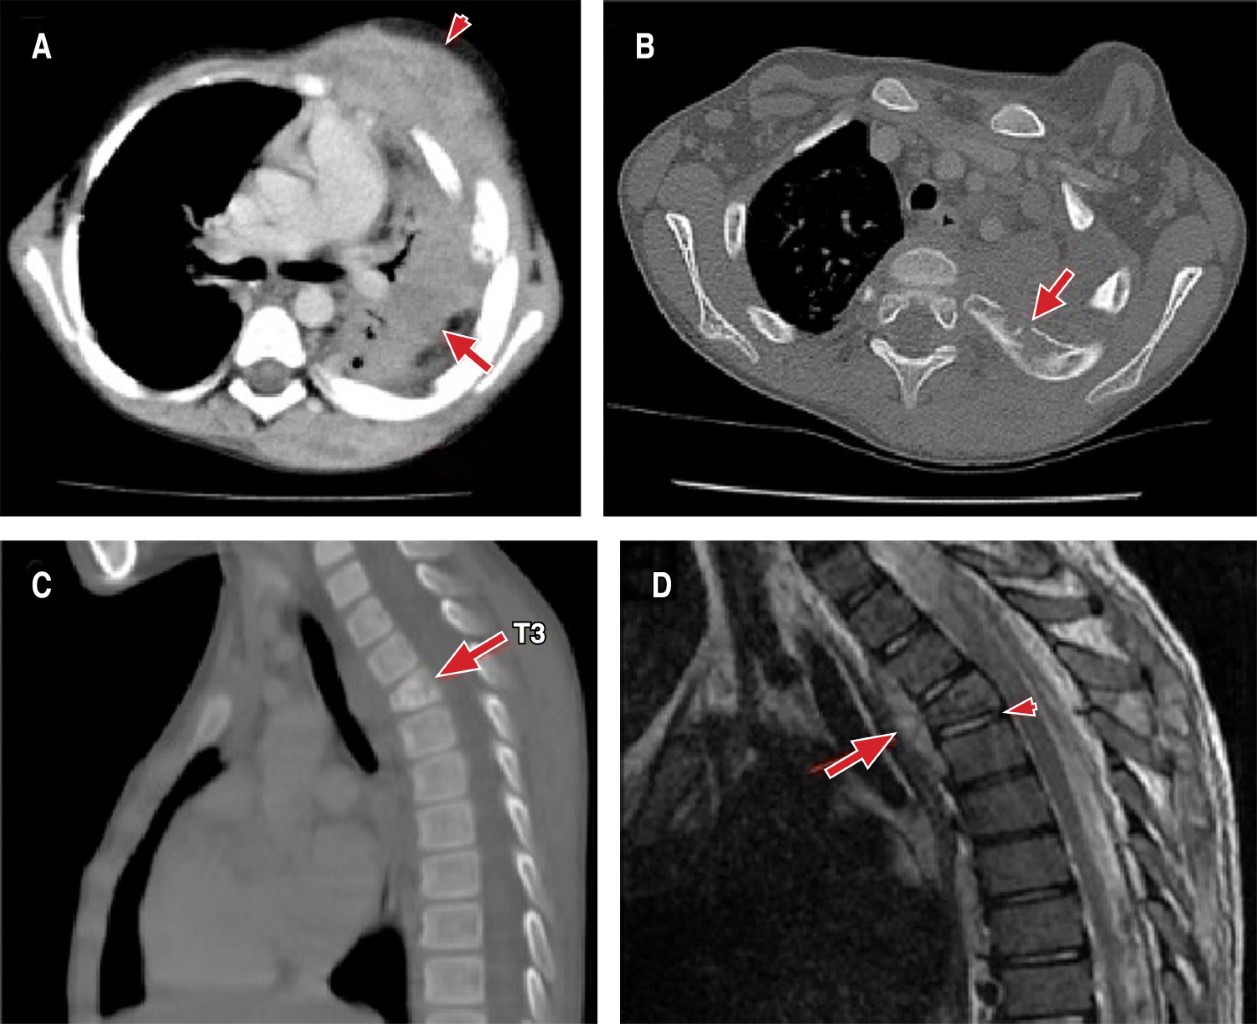

Se realizó tomografía de tórax, evidenciando zona de consolidación -sin realce- del lóbulo superior izquierdo con broncograma aéreo, sugestivo de neumonía necrosante. También se identificaron lesiones líticas en diferentes costillas del lado izquierdo, y lisis en la vértebra torácica T3, así como abscesos en región anterior y posterior del hemitórax izquierdo (Figura 2A-2C). Mediante imágenes de resonancia de columna cérvico-torácica se demostró compromiso de los tejidos blandos prevertebrales a la altura de T3, pero descartando problemas en el disco intervertebral T3-T4 (Figura 2D). Con estos hallazgos se llegó al diagnóstico de espondilitis en T3, osteomielitis de costillas y neumonía necrosante con empiema necessitatis secundario. Se inició manejo con clindamicina.

Figura 2